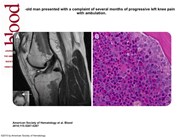

A 27-year-old man presented with a complaint of several months of progressive left knee pain with ambulation. An MRI scan of the left knee revealed extensive intermediate-low-signal intensity within the bone marrow in the diametaphyseal regions of the distal femur and proximal tibia (panel A, sagittal T2-weighted image of knee joint) and the epiphysis of the proximal fibula (panel A inset, coronal T1-weighted detail of fibular epiphysis; the arrow shows the bone marrow abnormality). The patient denied a history of knee trauma and was otherwise healthy. He had no knee abnormality on examination. There was no enlargement of lymph nodes, liver, or spleen. Laboratory tests showed a white blood cell count of 25.3 × 109/L with 55% neutrophils, 8% bands, 5% myelocytes, 6% metamyelocytes, 21% lymphocytes, 4% monocytes, and 1% basophils; hematocrit of 43.7%; and platelet count of 203 × 109/L. A bone marrow aspirate and biopsy from the left posterior-superior iliac crest revealed hypercellularity with granulocytic predominance (panel B). Karyotypic analysis revealed a Philadelphia chromosome (t (9;22)). The patient was diagnosed with chronic myelogenous leukemia (CML) and therapy with imatinib mesylate was initiated.

The abnormalities on the MRI scan, when viewed in the absence of known hematologic abnormalities, were initially attributed to red marrow reconversion, which may be secondary to athletic activity. However, similar findings can indeed be seen in myeloproliferative disorders and marrow replacement disorders. Clinicians should be aware of unusual presentations of hematologic disorders in seemingly healthy patients with abnormal bone marrow signal on MRI scans.